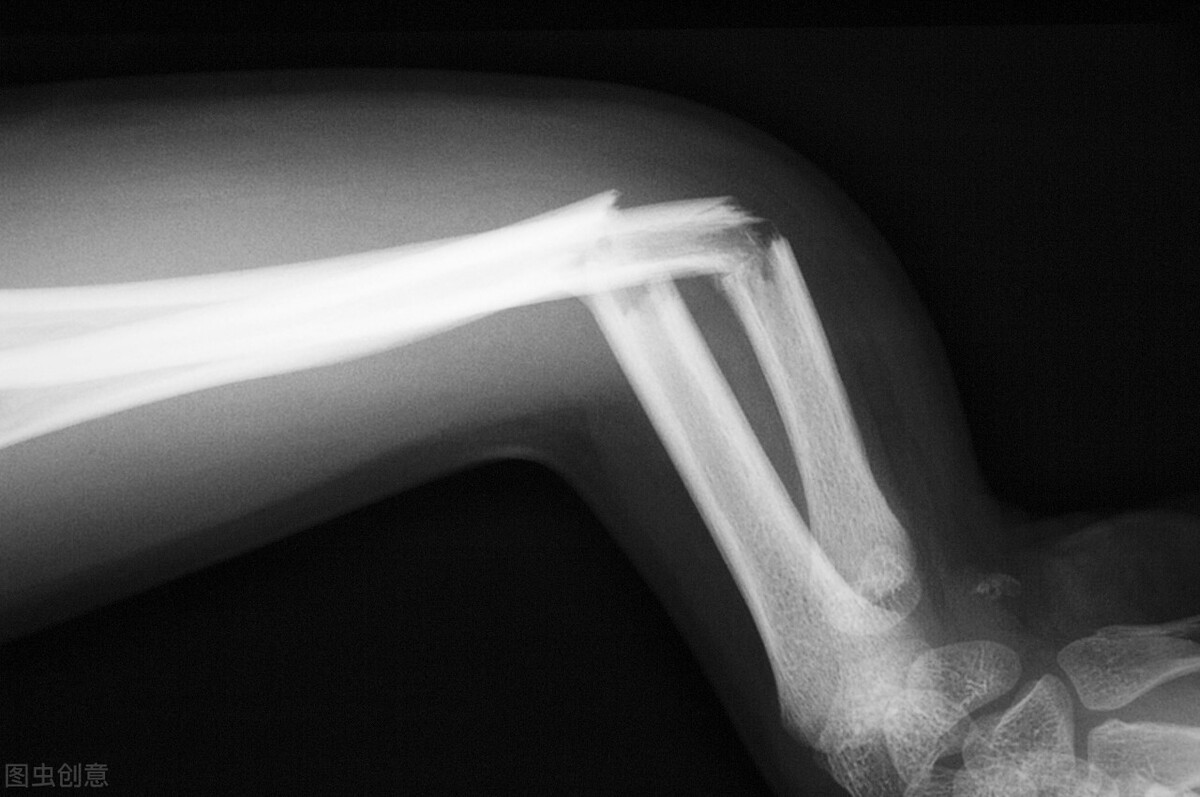

4月27日,上海一家医院收治了一名特殊的急诊患者。该患者为女性,在公司团建活动中掰手腕导致受伤,上臂肱骨被扭开花,经诊断为右臂上端粉碎性骨折,目前接受了钢板内固定手术。